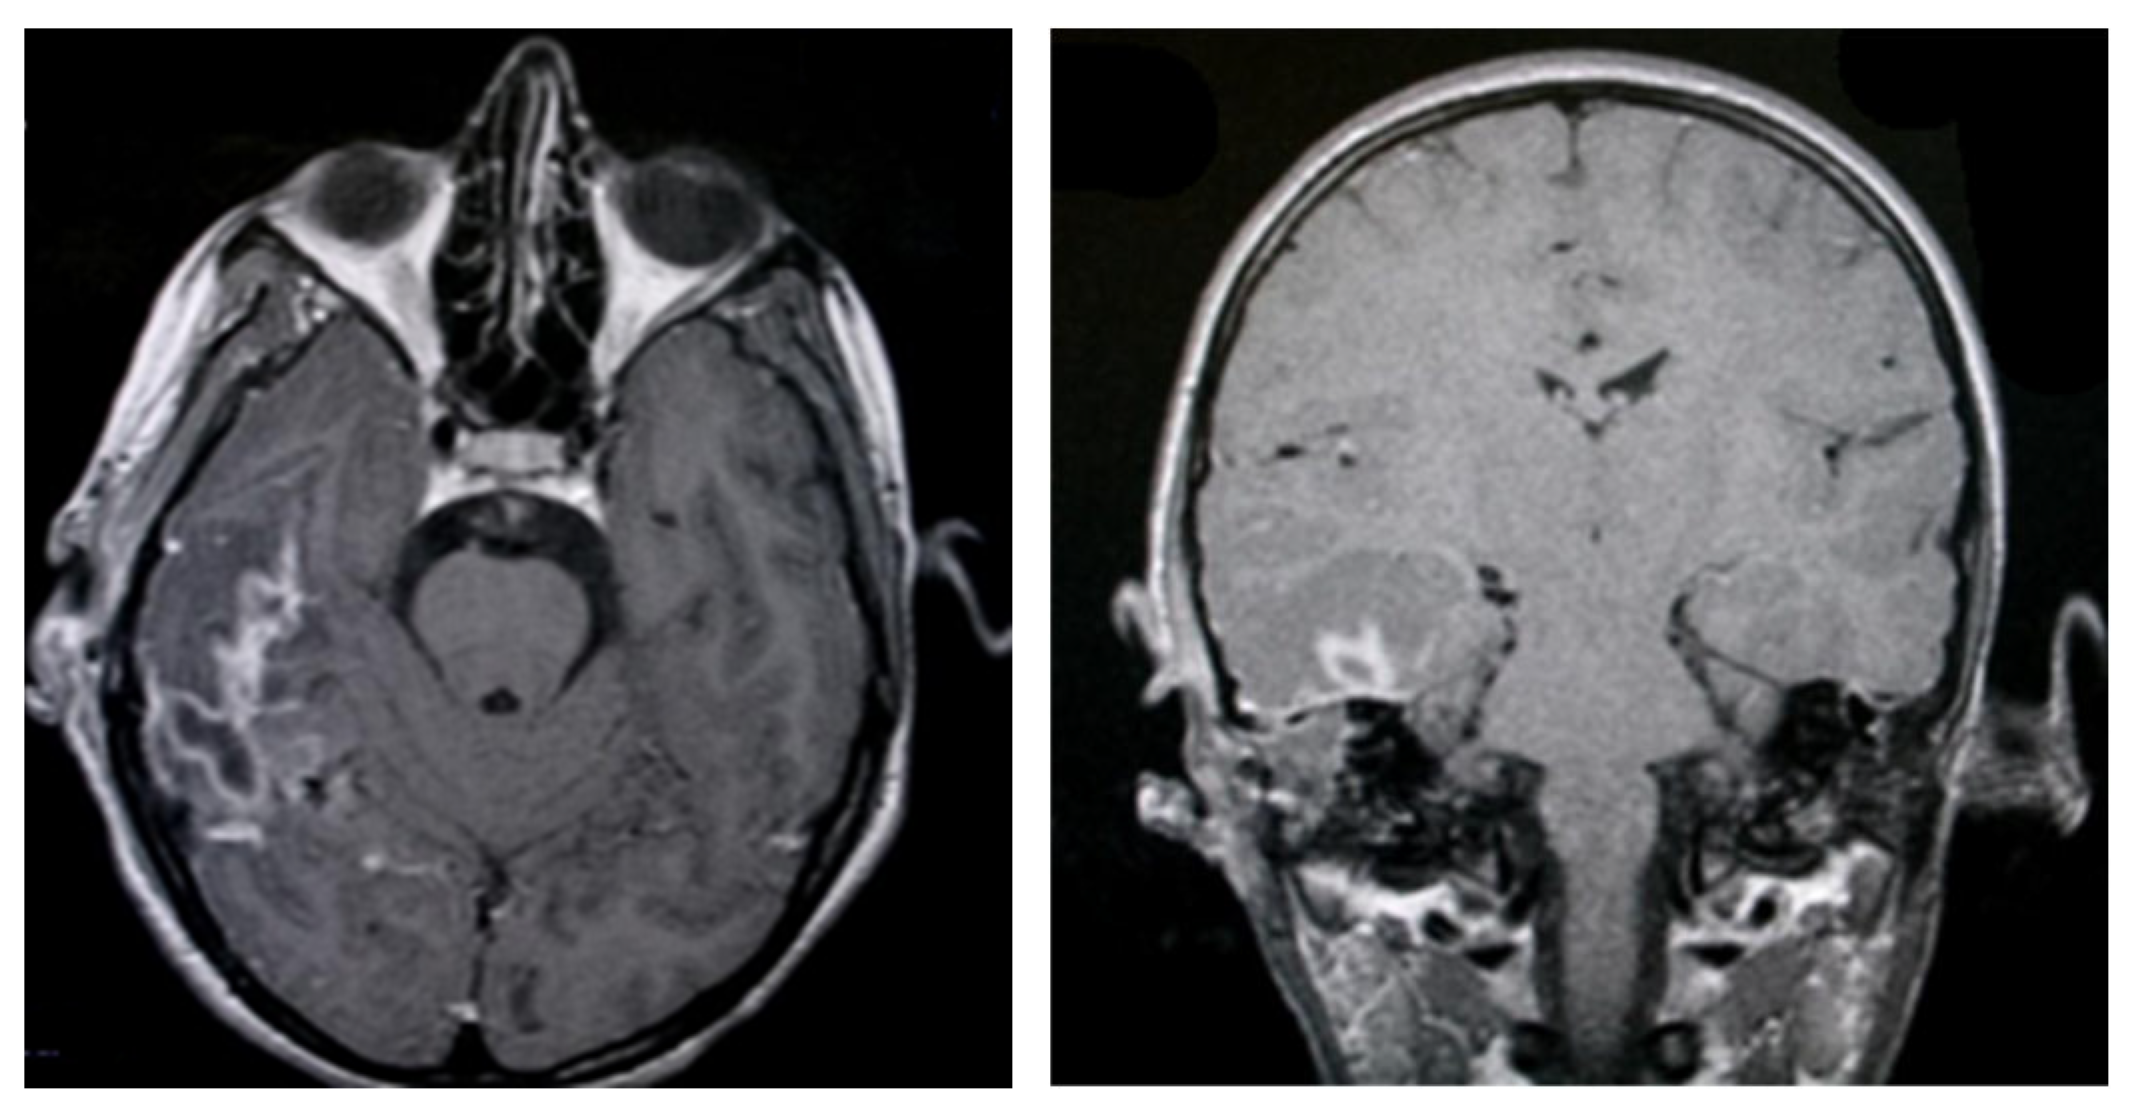

3.1.2. Computed Tomography and Magnetic Resonance Imaging

| MRI Aspects | Number of Patients | Percentage |

|---|---|---|

| Edema | 128 | 100% |

| Cholesteatoma | 40 | 31.25% |

| Exocranial extensions | 40 | 31.25% |

| Intracranial extensions | 32 | 25% |

| Inner ear damage | 20 | 15.62% |